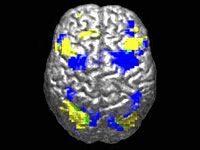

По данным исследования, ученые из Мичиганского университета создали ИИ-модель, способную анализировать МРТ мозга и выдавать диагностическое заключение за считанные секунды. Система определяла неврологические заболевания с точностью до 97,5% и оценивала, насколько срочно пациенту требуется медицинская помощь. По мнению авторов работы, эта технология может существенно изменить подход к нейровизуализации в американских медицинских учреждениях. Результаты исследования опубликованы в журнале Nature Biomedical Engineering.

При анализе более чем 50 радиологических диагнозов, связанных с основными неврологическими заболеваниями, модель Prima показала более высокую диагностическую точность по сравнению с другими современными ИИ-системами. Она также эффективно определяла, какие случаи требуют первоочередного внимания. По словам исследователей, при таких состояниях, как внутримозговые кровоизлияния или инсульты, где счет идет на минуты, Prima способна автоматически уведомлять медперсонал, чтобы ускорить оказание помощи.

Система также подсказывает, какого узкопрофильного специалиста следует привлечь – например, невролога по инсультам или нейрохирурга. Эта информация становится доступной сразу после завершения визуализационного обследования. Prima – это мультимодальная ИИ-система, которая умеет одновременно работать с изображениями, видео и текстом в реальном времени. Хотя ИИ уже применяли для анализа МРТ и других методов нейровизуализации, подход Prima отличается от предыдущих разработок. Ранее модели обучали на специально отобранных наборах МРТ-данных для решения узких задач – например, поиска очагов поражения или оценки риска деменции.

Команда пошла другим путем: Prima обучили на полном архиве МРТ Медицинского центра Мичиганского университета – это более 200 000 исследований и около 5,6 миллиона последовательностей, накопленных с начала цифровой эпохи в радиологии. Кроме самих снимков, в модель добавили клинические данные пациентов и информацию о том, почему врач назначил визуализационное исследование.

По словам авторов работы, система анализирует данные "как рентгенолог": объединяет сведения из истории болезни и результаты визуализации, чтобы получить целостную картину состояния пациента. Это повышает эффективность модели в самых разных прогностических задачах.